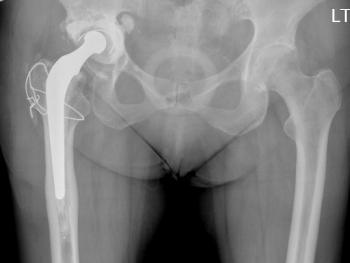

Clinical cases: variations of Exeter stem size and offset copes with almost all abnormal anatomies.

Figure 7 & Figure 8: DDH case with bowed femur and over-riding GT.

Figure 9 & Figure 10: DDH case – small socket – 40/22mm required. Leg length restored. Modularity of head sizes and offsets allows accurate restoration of leg length and offset.